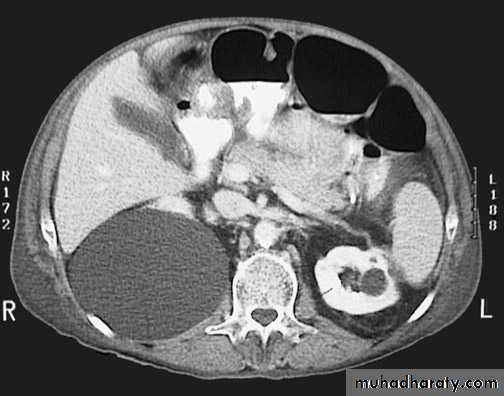

Congenital cystic kidney (polycystic kidney) (Adult cystic renal disease)

Both kidneys replaced by large number of cysts of variable size which make the kidney of large size.

The cysts contain clear fluid but sometimes blood.

The cysts progressively increase in size causing pressure atrophy of the renal parenchyma and pressing the ureter.

U/S, IVU, CT scan, MRI